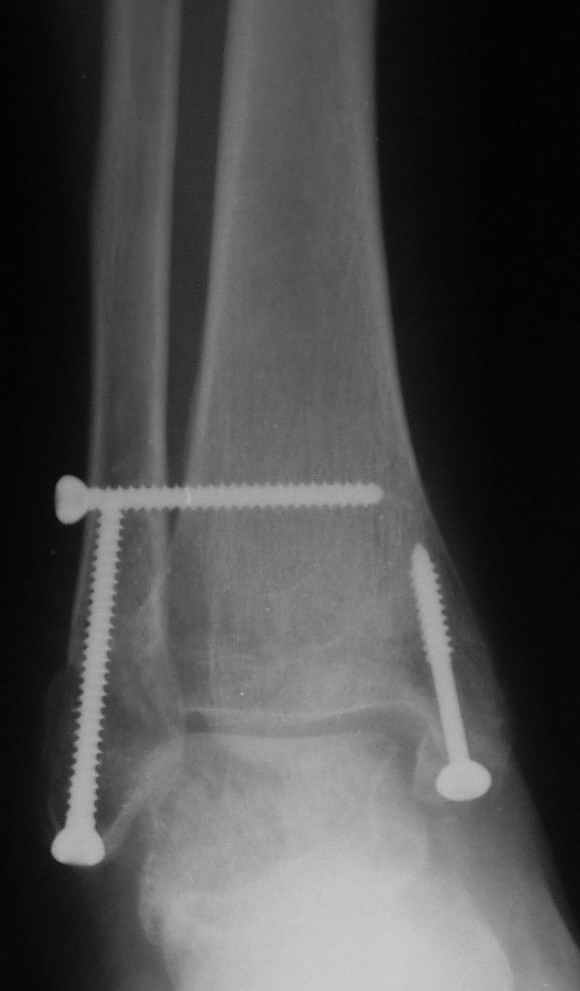

Через месяц